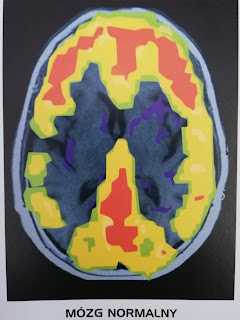

Przeanalizowano skany mózgów sprawców 41 morderstw i porównano je z obrazami normalnej aktywności mózgowej. Jeśli spojrzymy na skany mózgów osób, które nie popełniły morderstwa, to możemy zauważyć, że poziom aktywności w korze przedczołowej i korze potylicznej jest niemalże identyczny. Mózgi badanych morderców wykazują dużo większą aktywność kory przedczołowej niż potylicznej, a także znacznie zmniejszony poziom metabolizmu glukozy w korze przedczołowej w porównaniu z grupą kontrolną. To dowodzi, że zaburzenia w funkcjonowaniu kory przedczołowej u morderców są jednak faktem.